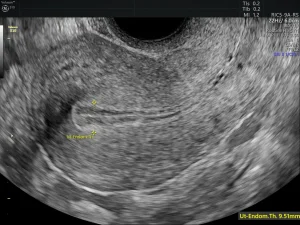

Read MoreEndometrial Hyperplasia: Symptoms, Causes, Diagnosis, and Treatment Home / Changes...